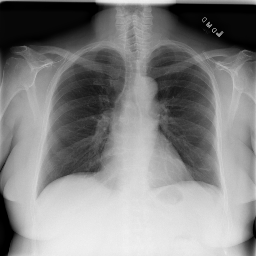

• Brain Tumor MRI Dataset (BMRI) [33]: The three datasets below are combined to create this dataset: figshare, SARTAJ, Br35H. There are 7023 MRI images of the human brain in this collection, divided into 4 categories: pituitary, glioma, meningioma, and no tumor. Images categorized as the ’no tumor’ class were obtained from the Br35H dataset.

• Chest X-ray Dataset (CXR) [34]: This dataset originates from the NIH, which is the largest chest radiograph data set. From 30,805 special patients, 112,120 frontal X-ray images are collected. Each X-ray is linked to the associated text disease label, which is drawn from the relevant radiological reports using an NLP algorithm.

• Lung Cancer CT Dataset (LCT) [35]: From different specialist hospitals, the IQ-OTH/NCCD lung cancer dataset was collected over three months in the fall of 2019. It comprises CT scans from patients with lung cancer in different stages and healthy subjects, totaling 1190 images from 110 cases. The dataset, marked by oncologists and radiologists, categorizes cases into three classes: normal (55 cases), benign (15 cases), and malignant (40 cases).

The proposed QMedShield’s security is evaluated using a number of metrics and proved that it is resistant to various cryptographic attacks including brute-force attacks, statistical attacks, histogram attacks, and differential attacks. Throughout the section, 6 sample medical images BMRI1,BMRI2,CXR1,CXR2,LCT1,LCT2𝐵𝑀𝑅subscript𝐼1𝐵𝑀𝑅subscript𝐼2𝐶𝑋subscript𝑅1𝐶𝑋subscript𝑅2𝐿𝐶subscript𝑇1𝐿𝐶subscript𝑇2BMRI_{1},BMRI_{2},CXR_{1},CXR_{2},LCT_{1},LCT_{2} are taken (2 images from each dataset) to show the performance comparison. The selection of MRI, X-ray, and CT images for the encryption task aims to demonstrate the versatility and effectiveness of our model across various imaging modalities, showcasing its applicability and robustness in diverse clinical scenarios. Figure 11 shows the selected sample medical images and their corresponding encrypted images.

Refer to caption

(a) BMRI1𝐵𝑀𝑅subscript𝐼1BMRI_{1}

(b) CXR1𝐶𝑋subscript𝑅1CXR_{1}

(c) LCT1𝐿𝐶subscript𝑇1LCT_{1}

(d) BMRI2𝐵𝑀𝑅subscript𝐼2BMRI_{2}

(e) CXR2𝐶𝑋subscript𝑅2CXR_{2}

(f) LCT2𝐿𝐶subscript𝑇2LCT_{2}

(g) E(BMRI1)𝐸𝐵𝑀𝑅subscript𝐼1E(BMRI_{1})

(h) E(CXR1)𝐸𝐶𝑋subscript𝑅1E(CXR_{1})

(i) E(LCT1)𝐸𝐿𝐶subscript𝑇1E(LCT_{1})

(j) E(BMRI2)𝐸𝐵𝑀𝑅subscript𝐼2E(BMRI_{2})

(k) E(CXR2)𝐸𝐶𝑋subscript𝑅2E(CXR_{2})

(l) E(LCT2)𝐸𝐿𝐶subscript𝑇2E(LCT_{2})

Figure 11: Selected sample plain medical images and the corresponding encrypted cipher images